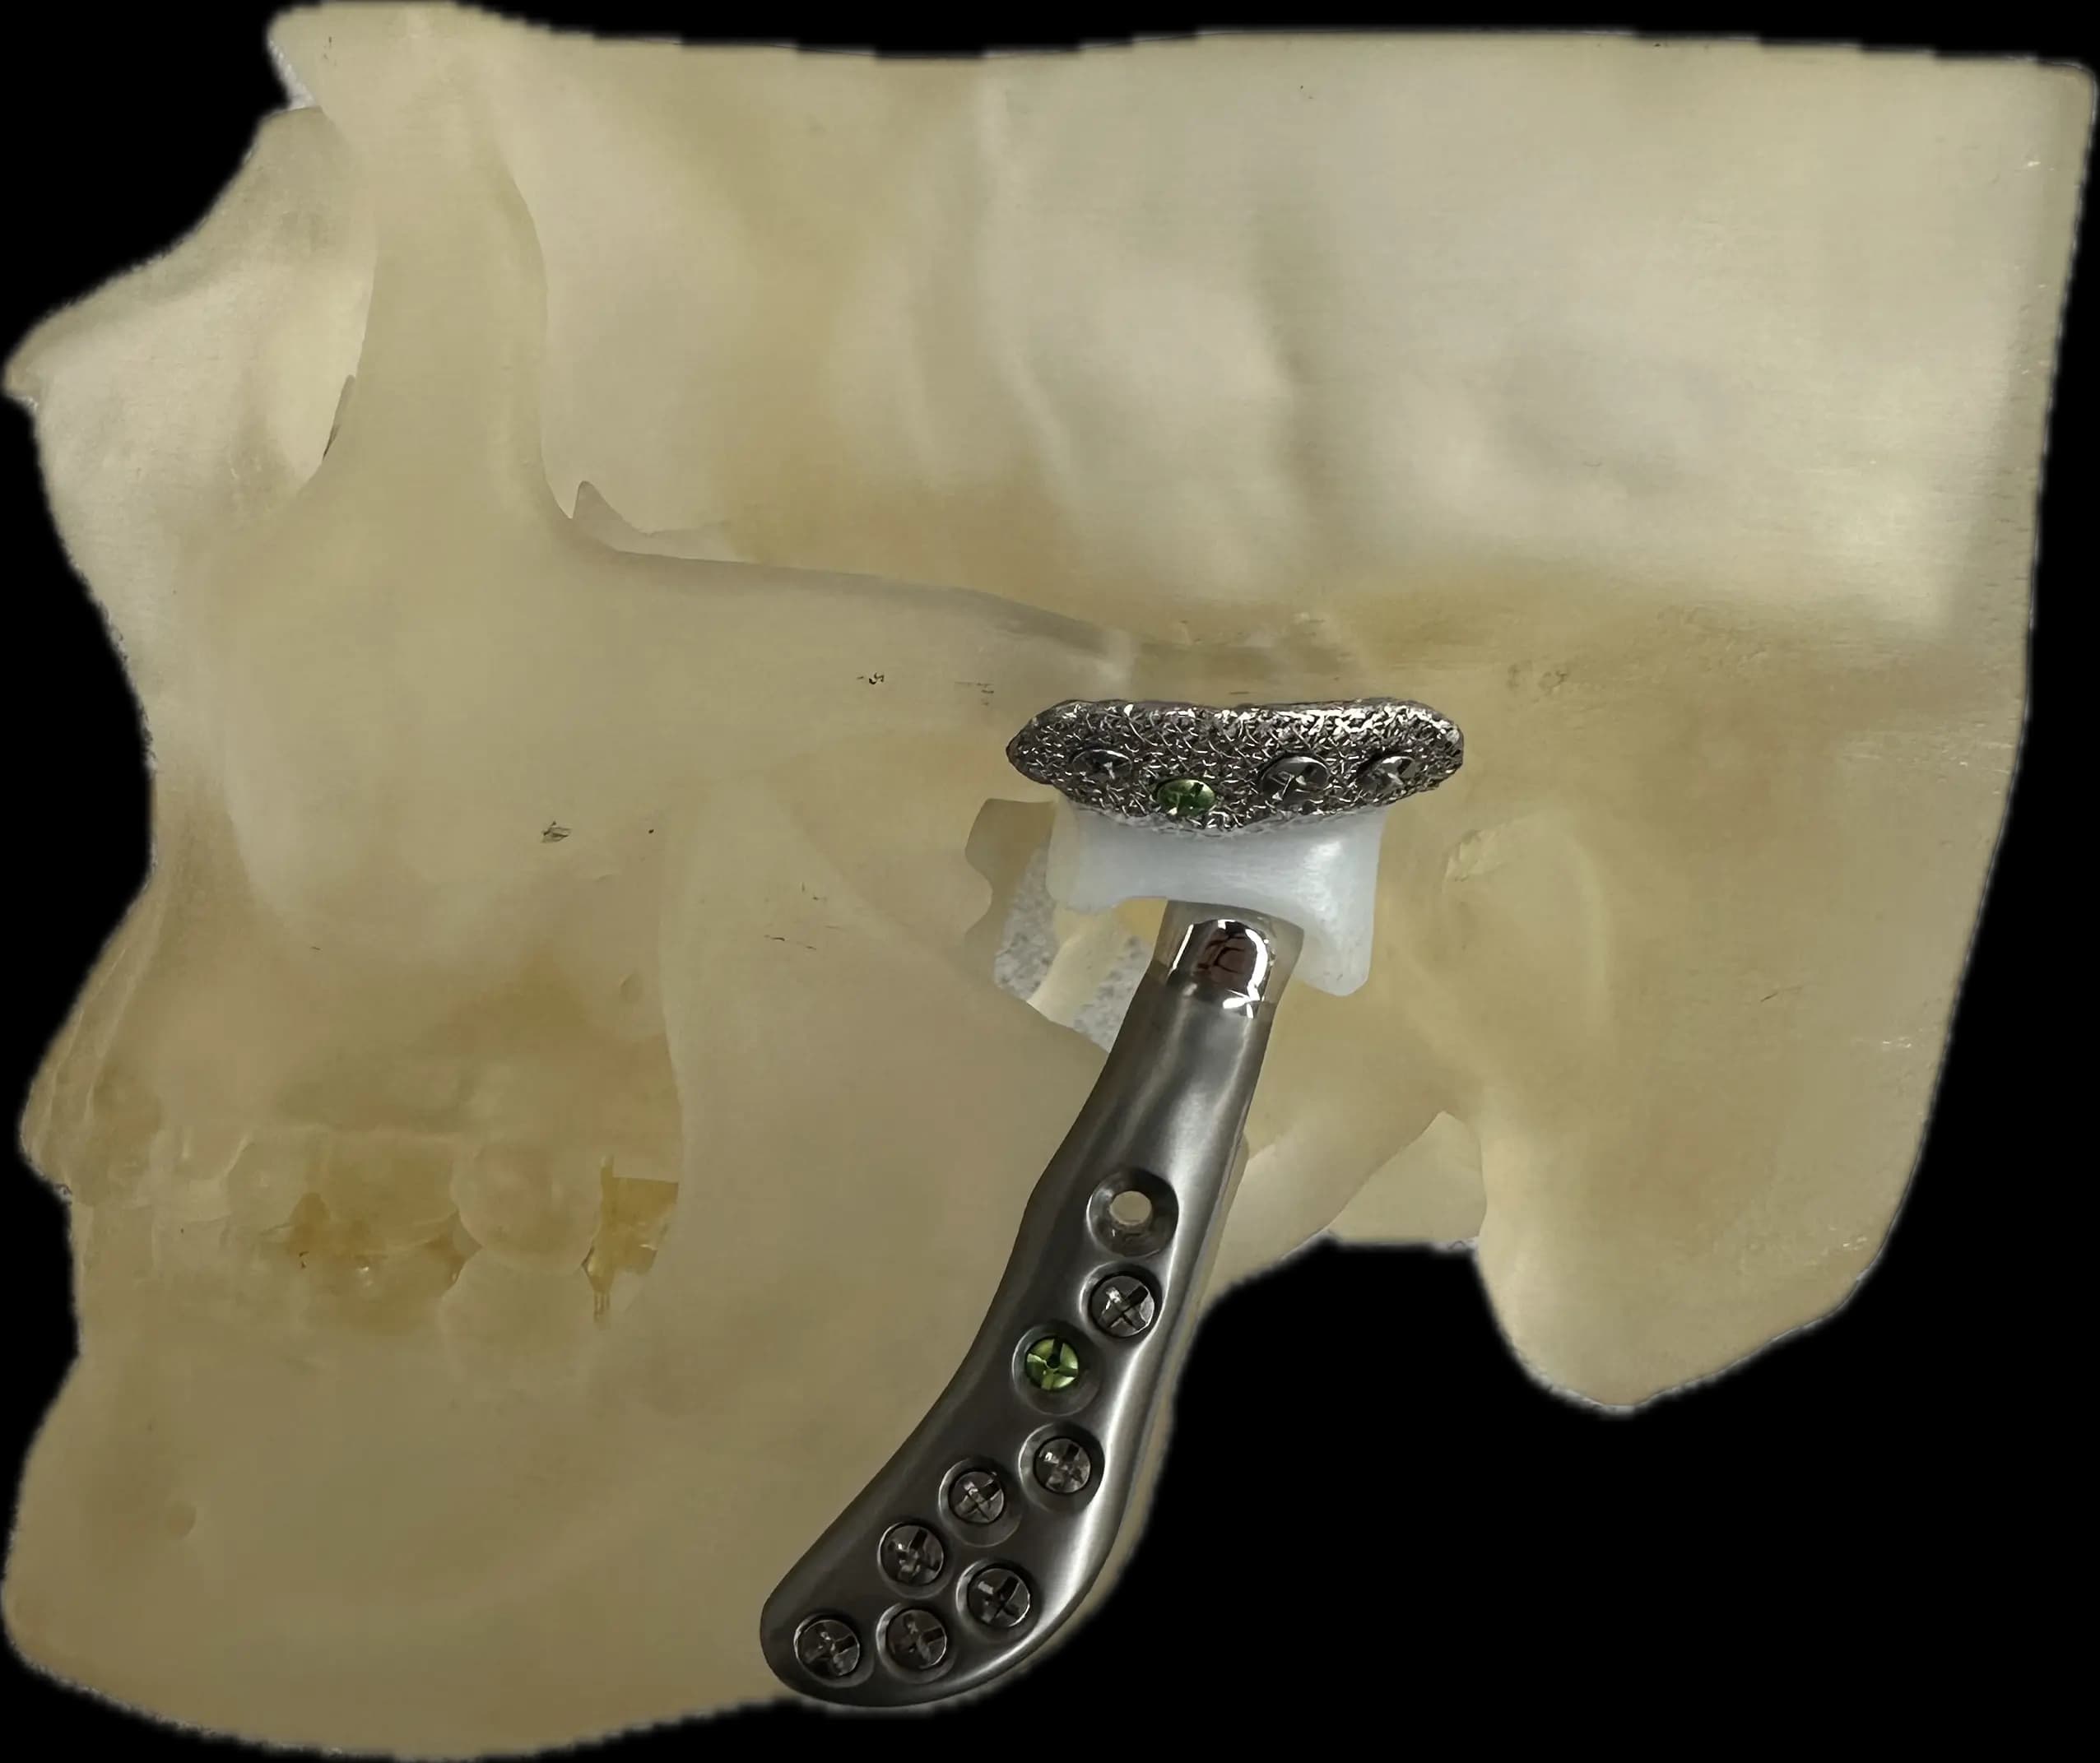

Certains DTM par contre nécessiteront une approche chirurgicale en raison de leur nature ou de l’impact significatif qu’ils ont sur la fonction. En règle générale, le chirurgien tend à choisir l’approche minimalement invasive qui est la plus appropriée dans les circonstances. Cela peut impliquer une simple infiltration articulaire, une chirurgie sous caméra (arthroscopie; approche qui permet d’avoir accès et manipuler le contenu articulaire sans avoir à ouvrir) ou dans certains cas une chirurgie ouverte (arthrotomie). Les Drs Poirier et Badri détiennent notamment des expertises dans ces champs de pratiques de par leur expérience et leur surspécialisation.

Remplacements articulaires